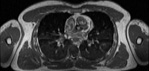

Visible Human male: Sectio transversalis 1421

CT

NMR

Pd                          / T2 \                         T1